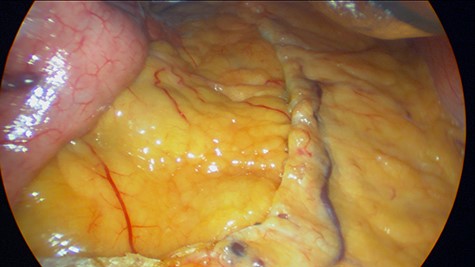

Patient is a 43-year-old female with past medical history of hypothyroidism and obesity. She sought surgical consultation since her body mass index (BMI) was high (36) and she had failed numerous attempts to lose weight over the past 10 years. Preoperative exams including an upper endoscopy were normal. LGS was planned. During the procedure, we used one 15 mm port, one 12 mm port and three 5 mm ports. A 30 telescope was used during the procedure to achieve visualization of the angle of his, a grasper was used as a liver retractor and a 36 French bougie was inserted to decompress the stomach. The incisura was located and a small window in the lesser sac was created 4 cm away from the incisura, the omentum was mobilized cranially, the bougie was advanced to the first part of the duodenum and staplers were used to create the sleeve. (Fig. 1) After this, the staple line was reinforced using a 3-0 synthetic absorbable monofilament suture (PDS 3-0, Ethicon, Johnson & Johnson). The specimen was retrieved from the 15 mm port, and the procedure was completed without complications. During the procedure, no lymph nodes or masses were seen. The patient underwent full recovery and was discharged without any apparent complications. Five days later, pathology reported that on the specimen, a small 4-mm polyp was detected in the staple line in the upper part of the fundus, a finding that was not detected on the previous endoscopy. After further evaluation, a grade II well-differentiated multifocal neuroendocrine tumor with vascular and perineural invasion was detected. Ki 67 index was 17% and 3/10 hpf mitosis were discovered (Figs 2, 3A and B).